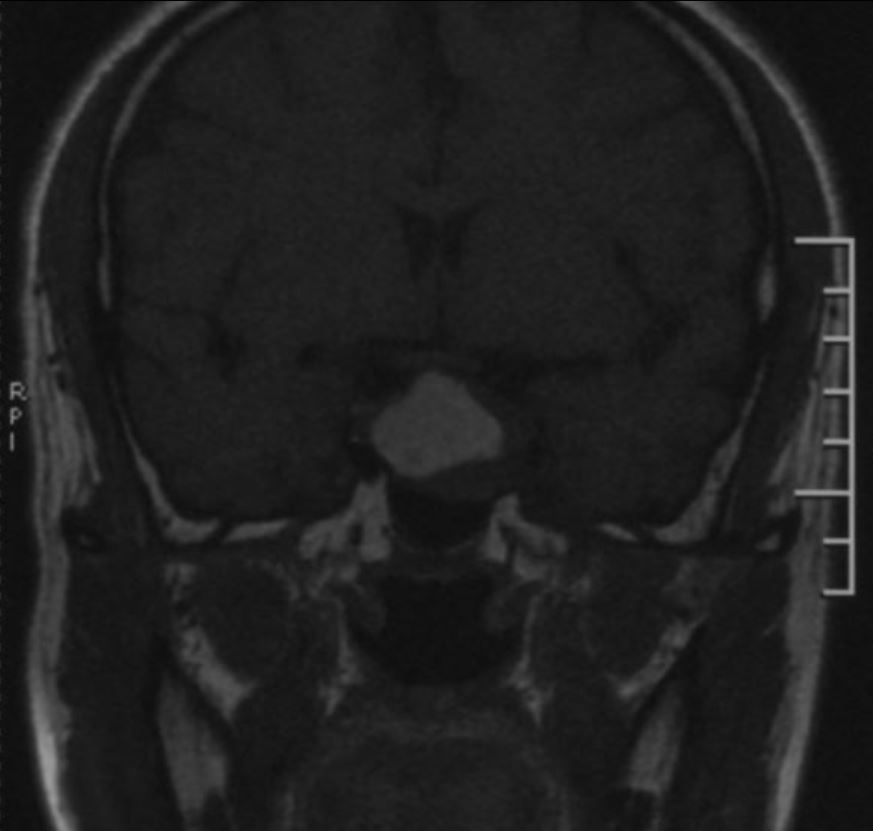

鞍区磁共振检查发现:鞍区肿瘤卒中可能,肿瘤侵犯双侧海绵窦、颈内动脉,鞍隔被顶起,鞍底部分塌陷。

TIWI像